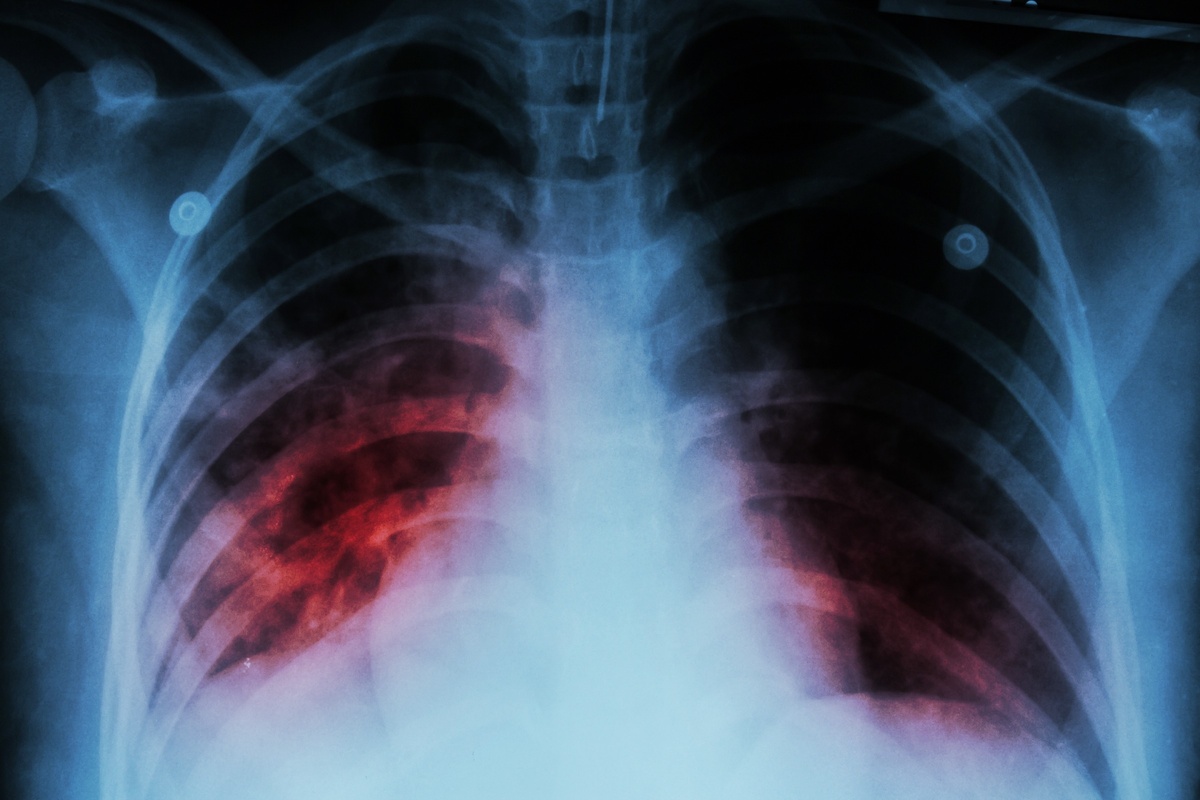

Туберкулез – одна из инфекций, плохо поддающихся лечению и нередко переходящих в хроническую форму. Несмотря на предпринимаемые усилия медиков, ежегодно в мире болезнь поражает более 9 млн. человек, а около 3 млн. больных погибает от различных осложнений.

В отличие от стран СНГ, в Европе и США к диагностике, лечению и профилактике туберкулеза применяется совершенно иной подход. Поэтому число случаев заболеваемости здесь гораздо меньше, а шансов на выздоровление у пациентов – больше.

Медики высокоразвитых стран отказались от пробы Манту из-за ее недостаточной информативности. И заменили тест анализами крови, которые позволяют ставить безошибочный диагноз. При их положительных ответах пациенту дополнительно проводят:

• КТ грудной клетки;

• анализ мокроты;

• эндоскопические исследования.

Всестороннее обследование позволяет точно установить тип патологии и выявить концентрацию возбудителя, что важно при выборе препаратов для лечения.

Также проводятся лабораторные исследования, которые помогают выявить устойчивость микобактерий к лекарственным средствам у конкретного пациента.